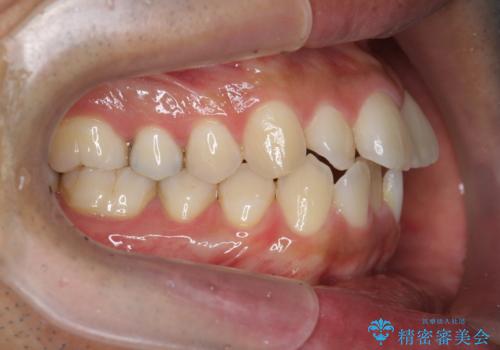

- 前歯のガタつきをきれいにしたい、と矯正治療を希望され来院されました。

マウスピース矯正インビザラインを用いてガタつきをきれいに並べていきます。

外側に傾斜していた前歯の角度も良くなり、「前歯の見た目が良くなった。」、と喜んでいただくことができました。